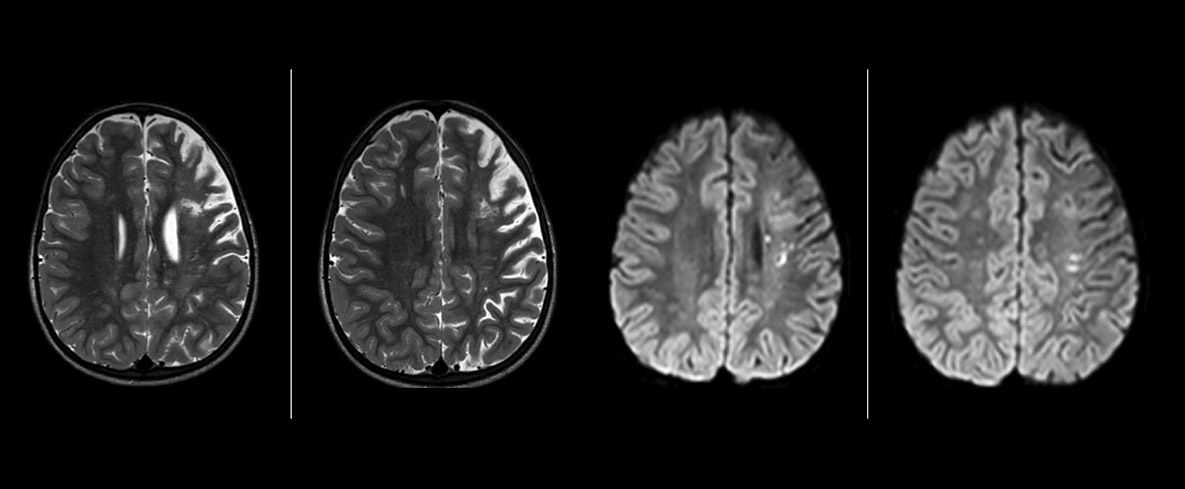

The value of susceptibility weighted imaging in visualizing brain injury is well documented. The Philips multi-echo SWIp technique provides fast susceptibility weighted imaging with enhanced susceptibility contrast and high resolution.

“Pediatric imaging is not without its challenges,” Dr. Miller says. “Since our patients are often very small, we need very high-resolution imaging. In cases of brain injury, we need to obtain information quickly so the treating clinicians can make decisions on care. We rely on high resolution and robust imaging capabilities, and SWIp provides that.”

“SWIp helps us identify blood or blood products, calcification, and diseases that affect the vascular system,” says Dr. Miller. “In children with traumatic brain injuries, it highlights areas that are injured, better than some of the previous techniques that we were using. These children often have micro-injuries that cause small amounts of blood or tissue damage. Adding SWIp helps us to better characterize the extent and nature of the injury. Having characterized an injury to the extent of what’s possible supports our diagnostic confidence.”

Full adoption after initial comparison

“I would definitely recommend other users to implement SWIp. We initially added the SWIp sequence following a lot of support for its utility in the literature. Then we directly compared SWIp to the 2D gradient echo sequences that we were using. After a good amount of clinical experience in seeing its benefits, we were confident to replace the old sequences with SWIp. It gives us a better assessment of the physiological processes of the brain that were less apparent on our previous imaging sequences,” says Dr. Miller. “SWIp is now a routine sequence for imaging traumatic brain injury patients at PCH, and it’s episodically added for patients who have intracranial vascular abnormalities.”

“I believe SWIp is rapidly becoming the standard in imaging traumatic brain injury, because of its high sensitivity to venous blood products. SWIp may even help attract patients; our neurosurgeons often ask to have the patients imaged on our scanners with highly sensitive techniques like SWIp. There’s also a growing application of SWI sequences in other vascular abnormalities because of the possibilities around physiological assessment of the brain than just a standard structural imaging.”